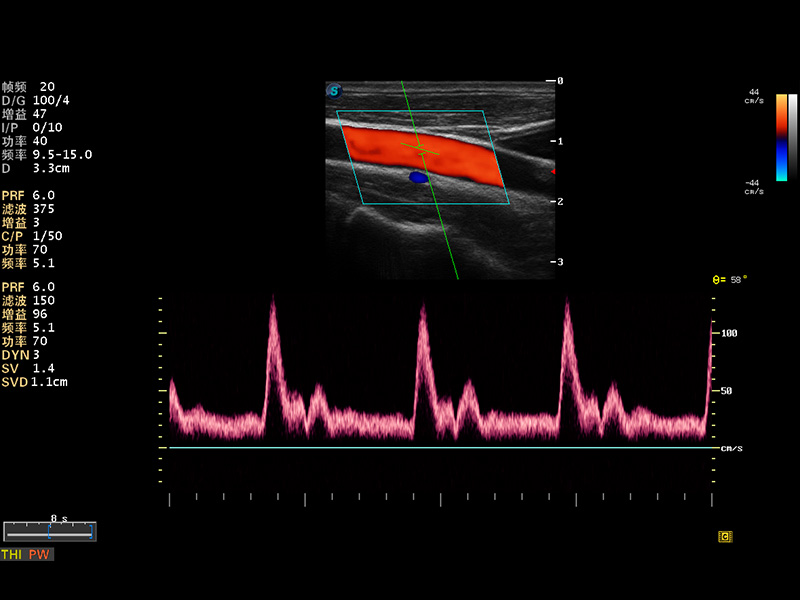

S8 EXP便携式彩色多普勒超声诊断仪是美狮贵宾会官网研发的高端全身应用型便携彩超。高通道的VIS平台融合可视化(Visual)、智能化(Intelligent)和人性化(Smart)的特点,配以美狮贵宾会官网自主研发生产的探头大家族,使您能够快速、准确的获得病人信息,提高工作效率的同时减轻疲劳。

成像技术

多波束形成器

μ-Scan微米成像

谐波成像

实时宽景成像

空间复合成像

3D/4D成像